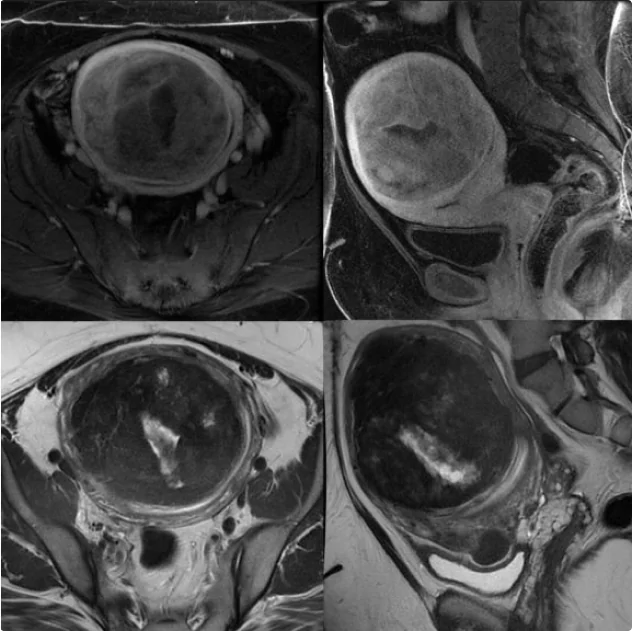

In diagnosing and preparing for uterine fibroid treatment, healthcare professionals conduct a thorough evaluation including the use of ultrasound or MRI equipment. They may require other tests, such as a laparoscopy or biopsy, especially if unusual bleeding is present. In preparing for UFE, it’s important to inform your doctor about any medication you take, allergies you have, recent illnesses you’ve experienced, or suspected pregnancies.